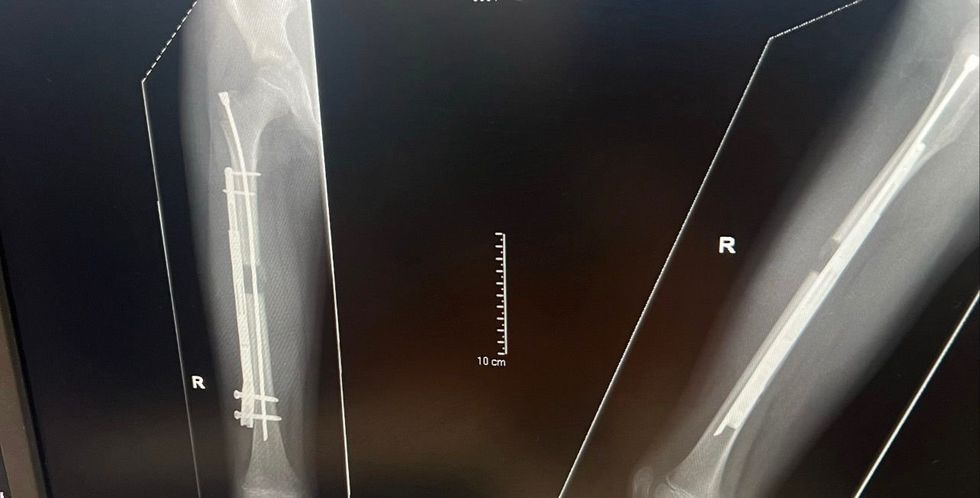

Surgeons at Alder Hey Children's Hospital in Liverpool fitted a lengthening nail to the surface of his right thigh bone.

Surgeons fitted a lengthening nail to the surface of his right thigh bone, which was gradually pulled apart using magnets

Doctors used a motorised telescopic nail, a technique developed in the US, placing it on the surface of his femur rather than inside the bone.

The bone was surgically cut and a rod inserted down the centre to keep it in line.

A magnetic device was then applied to Alfie's leg three times daily for a month.

This gradually separated the two bone ends by around one millimetre each day, allowing the body to fill the gap naturally with new tissue.

The lengthening process lasted around six weeks, with the nail removed three to four months after surgery.